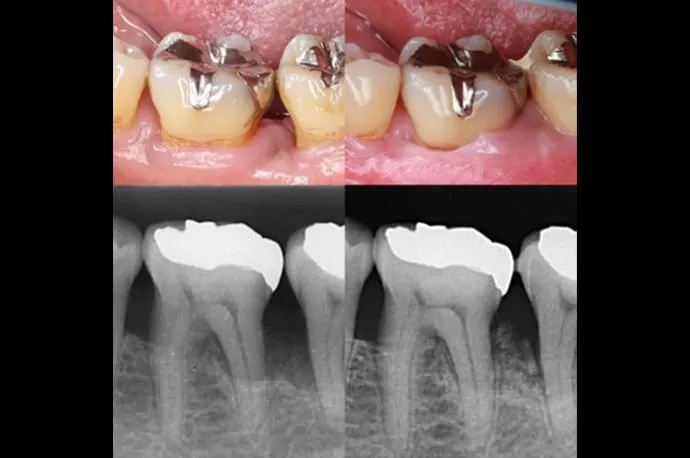

歯周基本治療の症例

治療前

治療後

歯周基本治療後の状態です。治療により歯ぐきの腫れや出血が改善し、炎症が落ち着いている様子が確認できます。歯石の除去によって、口臭やお口の中の不快感も軽減しています。

※歯周病によって歯ぐきが腫れていた場合、炎症が治まることで歯ぐきが引き締まり、治療前より下がったように見えることがあります。

※歯石除去後、一時的に知覚過敏の症状が出る場合があります。